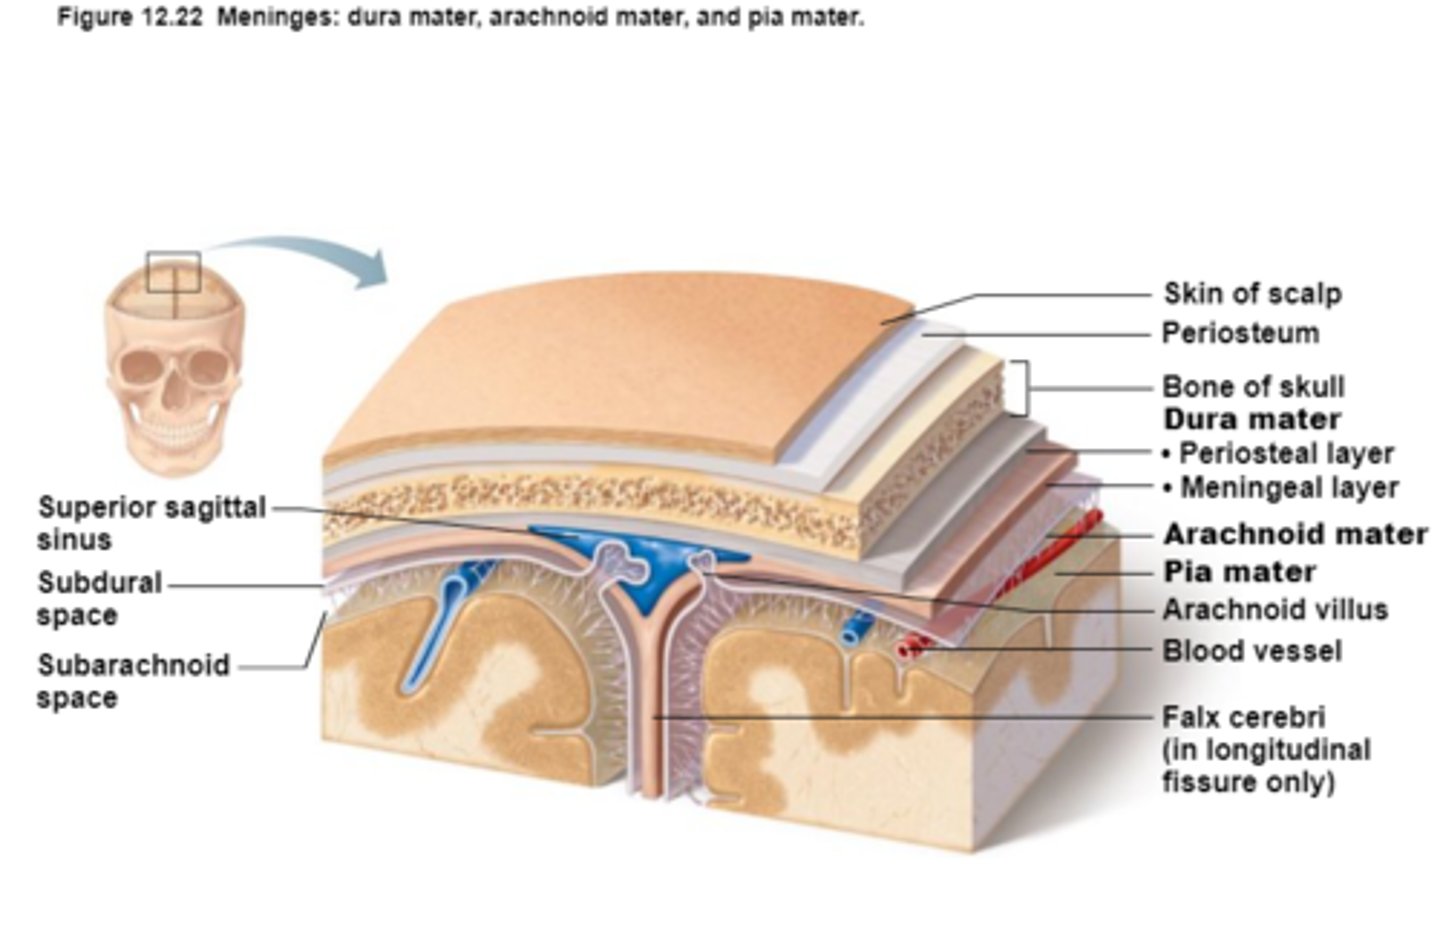

Protection of the CNS

1) scalp and skin

2) skull and vertebral column

3) meninges

Meninges

Connective tissue membranes that lie just external to the CNS organs that:

-Cover and protect the CNS

-Protect blood vessels and enclose venous sinuses

-Contain cerebrospinal fluid

3 Layers (external to internal) of Meninges

Dura Mater,

Arachnoid Mater,

Pia Mater

Dura Mater

First layer of Meninges,

Has layers that can separate to form dural sinuses:

-Periosteum

-Meningeal layer

Arachnoid Mater

Second layer of the Meninges,

Subarachnoid space with cerebrospinal fluid

Pia Mater

Third layer of Meninges